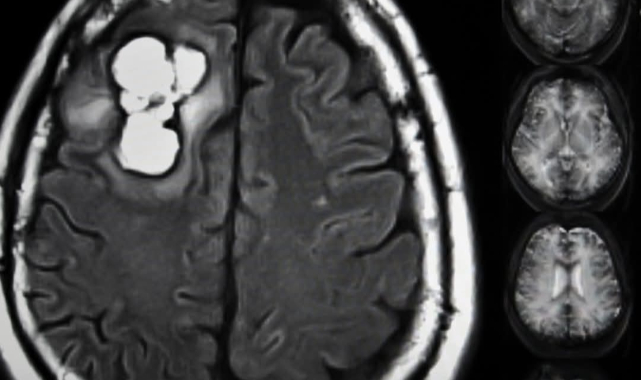

Uzman GörüşüAraştırmacılar, “Bu hastalık tanıdan sonraki iki yıl içinde hastaların büyük kısmını kaybettiriyor. Eğer klinik deneylerde de benzer sonuçlar alınırsa, glioblastom tedavisinde yeni bir dönem başlayabilir,” ifadelerini kullandı.